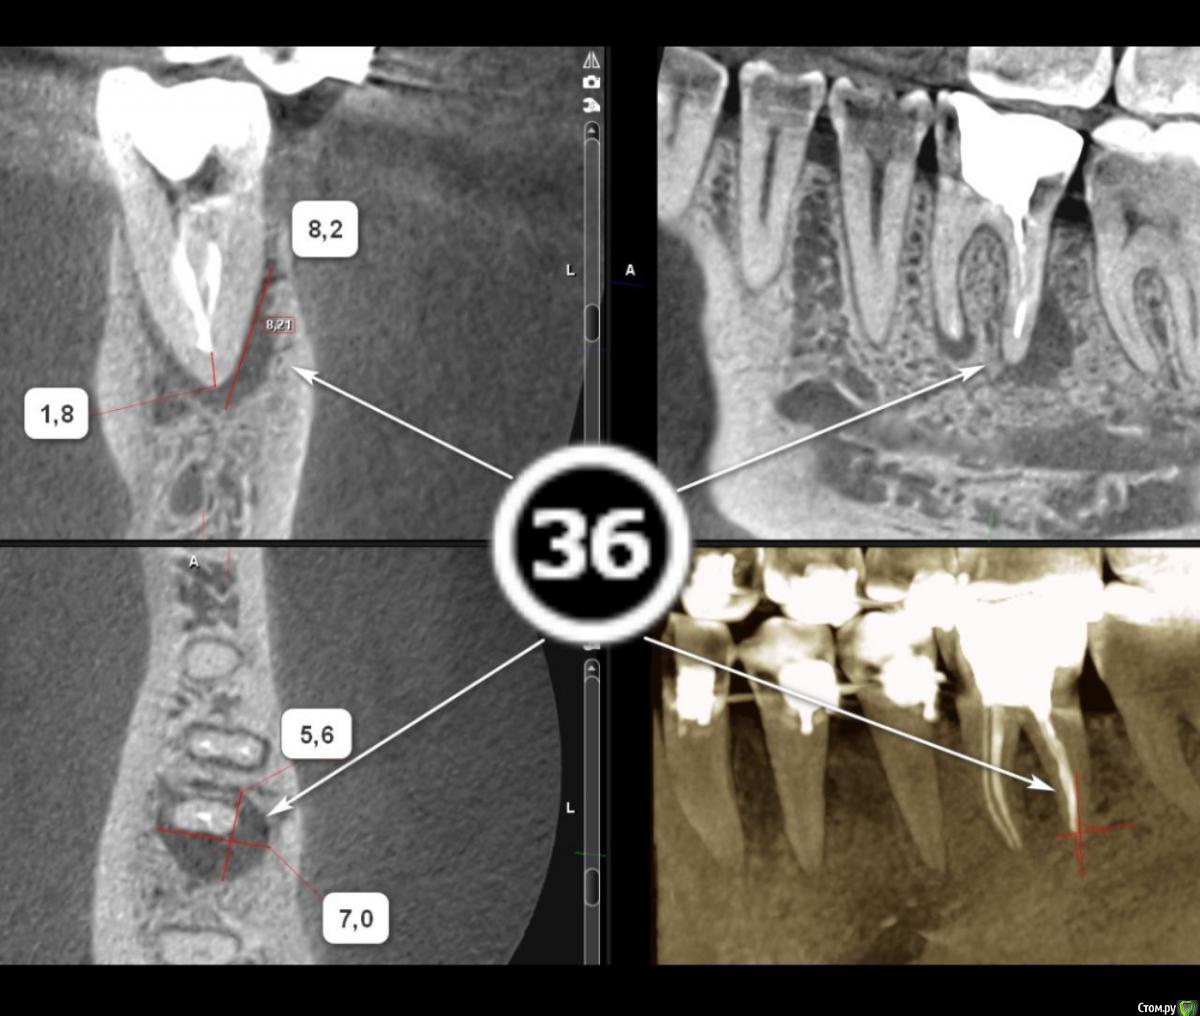

Tansky Опубликовано 18 марта, 2020 Автор Поделиться Опубликовано 18 марта, 2020 снимки - пара отпг до орто и актуальная, от 17.03.2020пара кт, в области интереса 3.6 и 4.7, разные снимки Ссылка на комментарий

Tansky Опубликовано 18 марта, 2020 Автор Поделиться Опубликовано 18 марта, 2020 разные проекции и описание заключения. прицельные rg есть еще по тому же зубу разных времен, но это надо искать дома и фоткать с негатоскопа или днем на свет Ссылка на комментарий